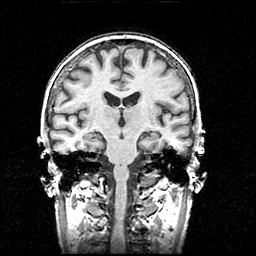

MR Study #1 -- Slice #62

[Home][Help][Clinical] Slice 62